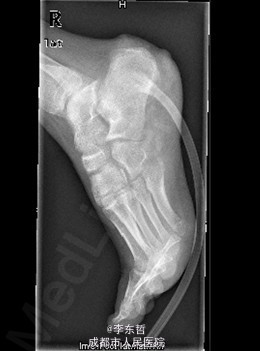

患者女,13岁4月,因“车祸致右足跟部皮肤撕脱伤清创缝合术后25天”入院。患者25天前因车祸导致右足疼痛流血伴功能障碍,右足跟部皮肤撕脱,遂到当地医院就诊,诊断为右足跟部皮肤严重剥脱伤,右跟骨骨折,右胫骨远端骨折。急诊下行“右足跟部皮肤严重剥脱伤清创缝合术”。术后给予止痛、消肿、预防感染等对症处理,目前右足外侧及跟部皮肤变暗,坏死。患者为进一步诊疗,故请我院远程会诊后转入我科继续治疗。患者病来精神、饮食可,大小便正常,体重未见明显改变。

查体:右足内踝、外踝及跟部皮肤变暗,部分缺血坏死。未见畸形,稍肿胀。触:右足趾皮温无明显降低,右足趾感觉未见明显异常。右足内踝、外踝及跟部皮肤局部压痛。动量:右踝关节活动受限,右踝关节活动诱发疼痛。右膝关节活动未见明显异常。 辅助检查:X线示:右跟骨骨折,右胫骨远端骨折。

初步诊断:1、右足跟部皮肤软组织撕脱伤清创缝合术后皮肤软组织大面积坏死伴感染;2、右跟骨骨折;3、右胫骨远端骨折;4、右足跖屈畸形。 处理:1、向患者及家属交待病情及注意事项。2、向上级医生汇报患者病情。3、完善相关术前等检查,择期行手术治疗。4、给予对症支持治疗。5、密切观察病情变化,根据病情及时处理。